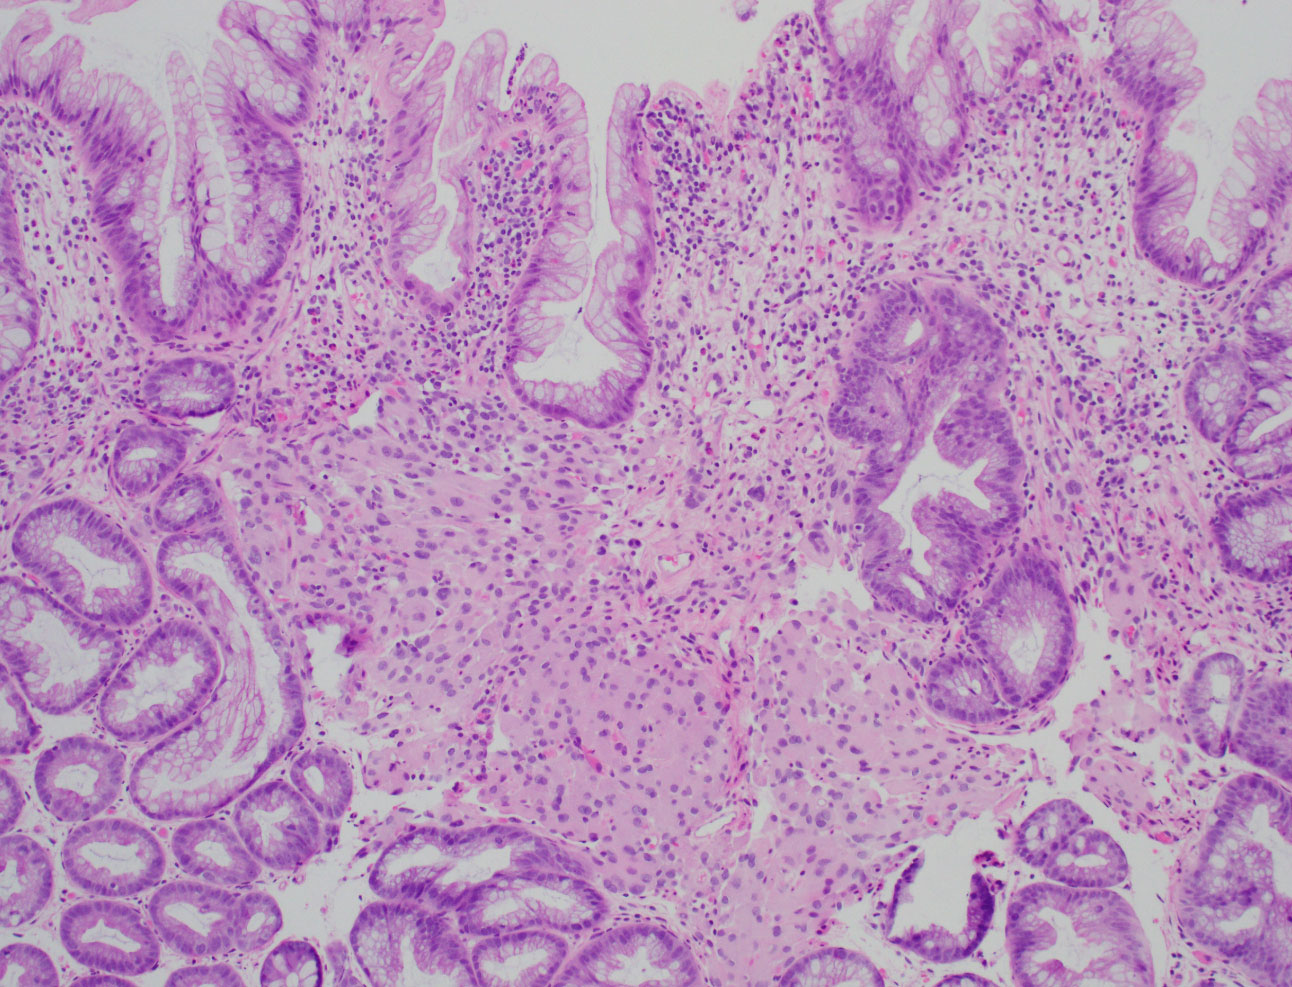

Screening colonoscopy demonstrated multiple polyps in the transverse colon and one diminutive (5 mm) polyp in the sigmoid colon. Histologically, the sigmoid polyp showed a hyperplastic polyp with an associated expansion of the lamina propria by a vaguely nodular proliferation of epithelioid cells. The epithelioid cells were arranged in small clusters with round nuclei, eosinophilic cytoplasm, and occasional nuclear grooves (Figures A-C). There was no cytologic atypia, mitotic activity, or necrosis. The epithelioid cells were positive for EMA (weak diffuse expression, figure D), while they were negative for pankeratin, GLUT1, S-100, SOX10, HMB45, DOG1, ERG, CD68, CD163, and SMA.